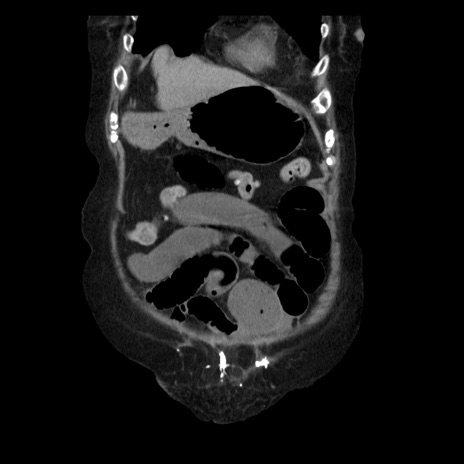

症例14(冠状断像)

【症例】 90歳代女性

【主訴】 腹痛・嘔吐

【現病歴】今朝から左側腹部痛を認めた。 経過観察していたが、嘔吐を認めたため来院。

【既往歴】 子宮癌術後

【身体所見】 意識清明、BP 127/54mmHg、P 98bpm Sp02 95%(RA)、BT 35.8°C、腹部平坦・軟腸ぜん動音聴取良好、右下腹部圧痛(+) 反跳痛なし

【データ】WBC 9800、CRP 0.46